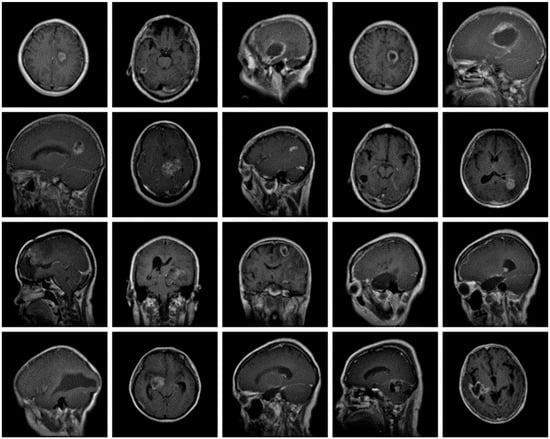

The dataset used for this current work is compiled from three other datasets: Figshare, SARTAJ, and Br35h. This composite dataset contains 2880 T1- weighted contrast-enhanced MRI brain images [26]. Gadolinium was used as contrast agent in these images. The target dataset has 829 images for glioma tumor, 825 images for meningioma tumor, 830 images for pituitary tumor and 396 images for no tumor cases. The images of the target dataset have a resolution of 512 × 512 × 3 with 24 bits color depth. Figure 1, Figure 2, Figure 3 and Figure 4 show some examples for each possible class: no tumor, glioma, meningioma, and pituitary tumor, respectively. The target dataset is split with 70% used for training and the remaining 30% kept aside for estimating the validation accuracy.

Figure 3.

Examples of MRI scans of meningioma tumors.